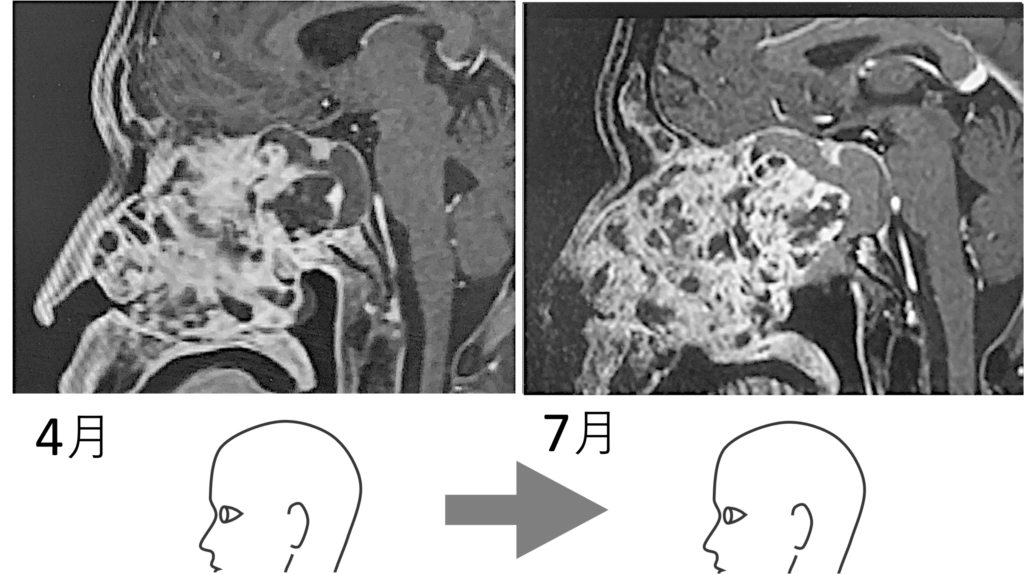

ガンの大きさはほぼ変わっていない。おそらくだが、ドクターは怪訝な思いであっただろう。3月にXデーは来ると予測したにも関わらず、進行が止まったのである。これは初診の血塊排出が大きく関わると見る。

いやよく見ると、わずかだが大きくなったようにも見える。下段で後述するが、このときすでにガン中心部の軟化は始まっていたと見る。見た目の画像では変化はないが、「かたい餅」から「やわらかい餅」へと変わり始めていたのである。やや大きくなって見えるのは、ガン自体が「ふやけてきた」のである。ふやけると、当たり前だが大きくなる。そして、それは悪いことではない。カチカチのままでは体外に排出できないからである。

1月から4月にかけてやや大きくなったかに見えたのは気のせいではなかった。明らかにガンは大きくなっている。その証拠が、耳が聞こえなくなり、左顔面が痺れ、ついで目が見えづらくくなったという現象である。

3月に倒れると宣告を受けた。しかし生きている。すなわち、脳幹 (青で塗りつぶした部分) には近づかず、逆方向の鼻孔や額部に張り出してきていることが画像から分かるのである。ガンがふやけてきた (軟化してきた) から大きくなってきているのであり、大きくなることは必要なのであるが、命の根幹である脳幹を避けるようにして大きくなっているのである。生き続けようとする生命は、こういうことをやってくる。都合のいいように、柔軟にかわしたり変化したりする。決して偶然ではないのである。そういう「印象」を僕は持つのである。それは下リンクのような奇跡を経験してきたからそう思うのである。